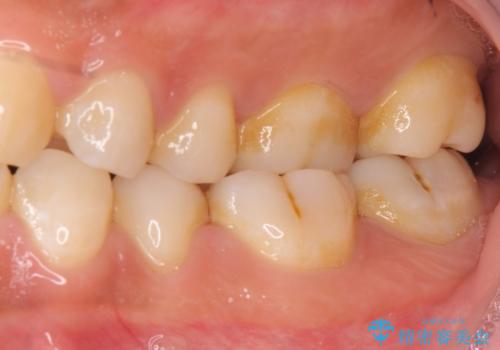

古い詰め物を取り、虫歯を除去して、合わせた形でセラミックインレーで治療しました。

- 14万円(内訳 左下67:セラミックインレー 7万円 x 2本)費用は治療当時の料金となります